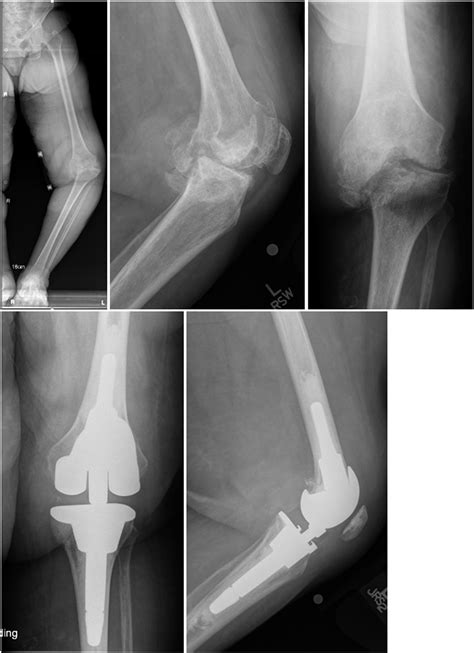

Knee Arthrosis. Unhealthy Knee Structure. Bone Exposure, Damaged Knee ...